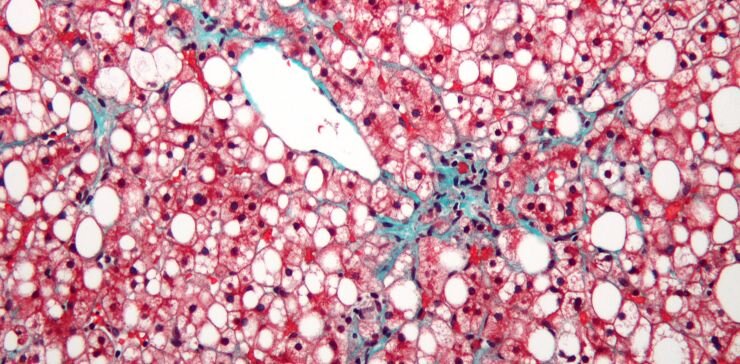

Неалкогольная жировая болезнь печени характеризуется накоплением капель жира (белый цвет) и умереннымй фиброзом (зеленый). Клетки печени – гепатоциты, окрашены красным